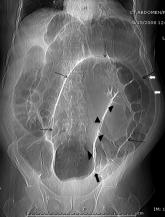

Sigmoid Volvulus